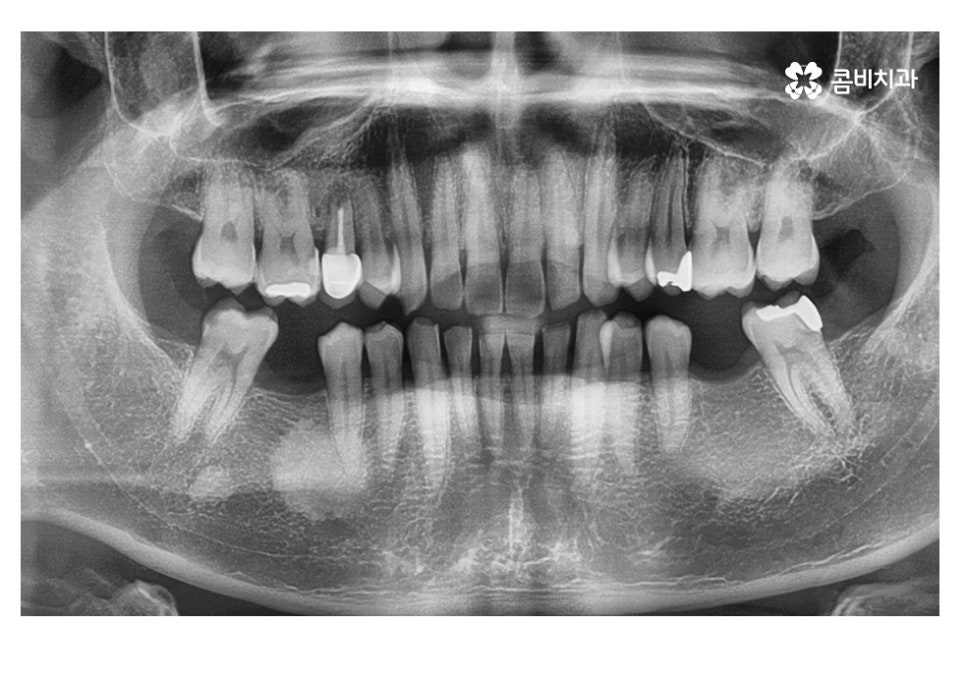

위 사례 이미지에서 보시는 것과 같이 불규칙한 치열 외에도

치아 사이가 벌어져 있으면 심미성 뿐 아니라

음식물이 치아 사이에 끼기 쉽기 때문에 충치, 잇몸질환이

발생하기 쉬울 수 있어요.